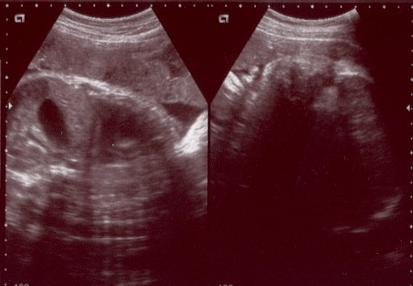

今日は妊娠37週目の健診でした。妊娠生活最後?の超音波スキャンもしていただきましたそのとき撮影していただいた画像です。。。相変わらず、分かりづらいです左側が胸部から腹部、右側が頭部です。ベビ子は、いつも私のお腹の方(外)を見ているようで、毎回スキャンのときは顔がはっきり見えますあごや首をしきりに動かして「狭いよう~」とでも言いたげでしたDr.のお話では、先週よりもさらに下がったようですが、全体としては「まだ半分ぐらいしか下がっていない」らしいです「この調子なら予定日前後だろうねぇ」と言われました。さて、問題のベビ子の大きさですが、推定体重がなんと3457g!!でございました。予定日まであと2週間もあるので、もしかするとかなりデカイ赤ちゃんになってしまうかもしれません夫は6ポンド(2700g)と小さ目の赤ちゃんだったようですが、私は3390gあったらしく、結構大きめに生まれてきています。ベビ子はどうやらパパではなく、ママの血を多めにもらっちゃったらしいです頭の直径は9.51cmとほぼ標準のようですとにかく、あまりデカイと出産が大変そうなので、大きくなりすぎないでくれ~と願うばかりですランキング参加中